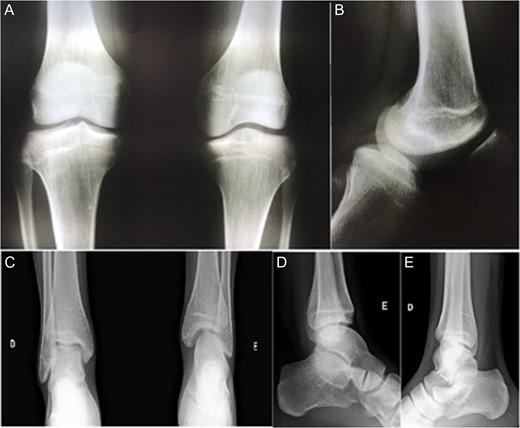

Radiographic images of the knees in AP (anteroposterior) and Lateral views and the panoramic of lower limbs (Fig. 1) were taken and confirmed a case of type 1 A fibular hemimelia on the affected side.

AP radiographic view of the knees (A) and lateral view of left knee—affected (B). AP (C) and lateral view (D and E) of the ankles. Note in (A) tibial spines hypoplasia of left knee, and in (C) left tibiotarsic joint dysplasia with fibular shortening, also noted in (D).